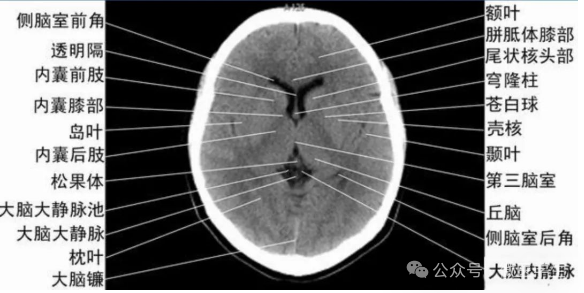

显示侧脑室前角的下部:

- 前方—额叶;外侧—尾状核头部;后方中线处—第三脑室,其两侧连接丘脑。

- 基底核、丘脑。

- 内囊前脚(前肢);尾状核和豆状核之间。

- 内囊膝部和后脚(后肢):位于豆状核(由外侧的壳核和内侧的苍白球组成)及丘脑之间。

- 壳核的外侧:外囊、屏状核、最外囊、岛叶(脑岛)。

- 四叠体池:两侧枕叶之间,池内有松果体,向前与第三脑室连接。

基底节(基底核):

- 埋藏在两侧大脑半球深部的灰质核团,是组成锥体外系的主要结构。

- 内囊:位于丘脑、尾状核、豆状核之间的白质区,是由上、下行的传导束密集而成。分为三部分:前肢、膝部、后肢。膝部由皮质脑干束;后肢有皮质脊髓束、丘脑皮质束、听辐射和视辐射。

- 外囊:是位于屏状核和豆状核之间的白质带,主要由岛叶发出的皮质被盖纤维组成。

由额、颞、枕叶构成,两侧侧脑室体部之间为透明隔,外侧为尾状核和体部。侧脑室后角(枕角)可不对称,室内可见脉络丛钙化。中线处可见大脑纵裂池和大脑镰。

内侧壁侧脑室体部被胼胝体分开,侧脑室体部的外方为顶叶,顶枕沟及中央沟将大脑为为额、顶、枕叶。